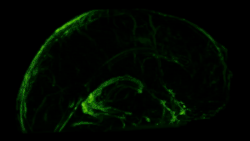

Confocal micrograph of meningeal lymphatic vessels and trafficking immune cells. LYVE1 (green), CD3e (red), and DAPI (blue) are shown.

Like peripheral lymphatic vessels, the meningeal lymphatics serve both the tissue drainage and immune cell trafficking functions of the lymphatic system. Multiphoton live imaging experiments performed on anesthetized mice have demonstrated that the meningeal lymphatics are capable of draining fluorescent dyes injected intracisternally into the CSF, indicating that the meningeal lymphatics are capable of draining fluid from their surrounding environment. Histological analysis revealed that the meningeal lymphatics constitutively contain T cells, B cells, and MHC class II-expressing myeloid cells, demonstrating that meningeal lymphatic vessels are capable of carrying immune cells.[1]